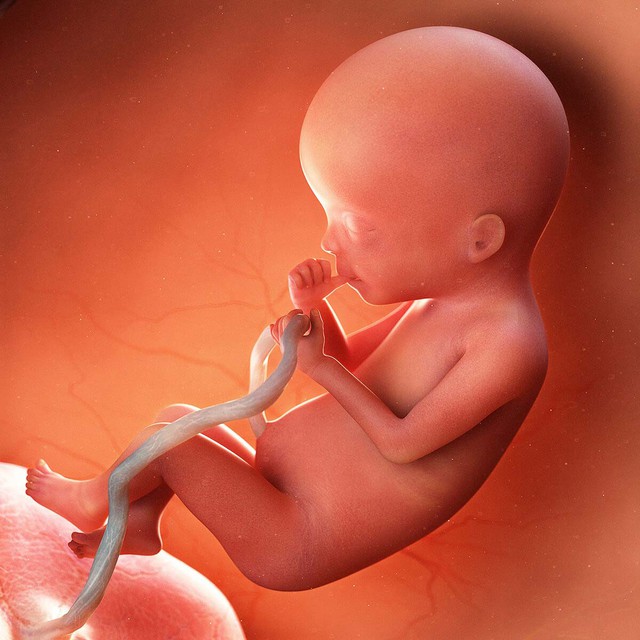

Bé yêu

– Bé yêu là một thai nhi, dài khoảng 15-16 cm (như quả chuối), nặng 250-300g, với tim đập mạnh (120-160 lần/phút).

– Phổi bé phát triển, chuẩn bị cho hô hấp sau sinh. Giác quan nghe, nhìn, và sờ nhạy hơn; bé phản ứng với tiếng nói mẹ hoặc ánh sáng mạnh. Lớp vernix (chất gây) dày hơn, bảo vệ da trong nước ối.

– Siêu âm cho thấy bé cử động đều đặn (đá, xoay, nấc cụt), ngón tay/chân hoàn thiện, và lông mi/mày rõ nét. Thật tuyệt vời!